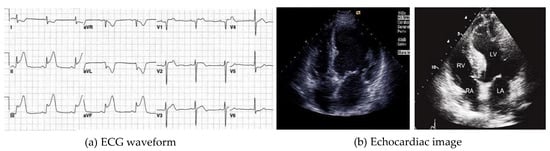

From UCI Machine Learning Repository we downloaded the Z-Alizadeh Sani dataset used by us. The Z-Alizadeh Sani dataset is the latest dataset with multiple examination indicators. This dataset contains 303 medical records derived from 303 cases who visited Shaheed rajaei hospital because of chest pain. Each record includes 55 features belonging to four categories. Four categories are demographic features; symptoms and physical examination; ECG; and laboratory tests and echocardiography features. A record is a sample. These 303 samples belong to two classes, namely, CAD class and normal class. When the stenosis of coronary arteries lumen of a sample reaches or exceeds 50%, this sample is classified as CAD class; otherwise it belongs to the normal class. Accordingly, in 303 samples, 216 instances accounting for 71.29% are CAD class, and 87 instances accounting for 28.71% are normal class [30]. Details of the Z-Alizadeh Sani dataset are shown in Table 2. To intuitively explain the features of Z-Alizadeh Sani dataset, in Figure 2, we showed an ECG waveform and an echocardiac image. The ECG features of Z-Alizadeh Sani dataset are obtained by professional doctors analyzing the ECG waveform in Figure 2a. Similarly, the echocardiography features of Z-Alizadeh Sani dataset are obtained by professional doctors detecting the echocardiac image in Figure 2b.